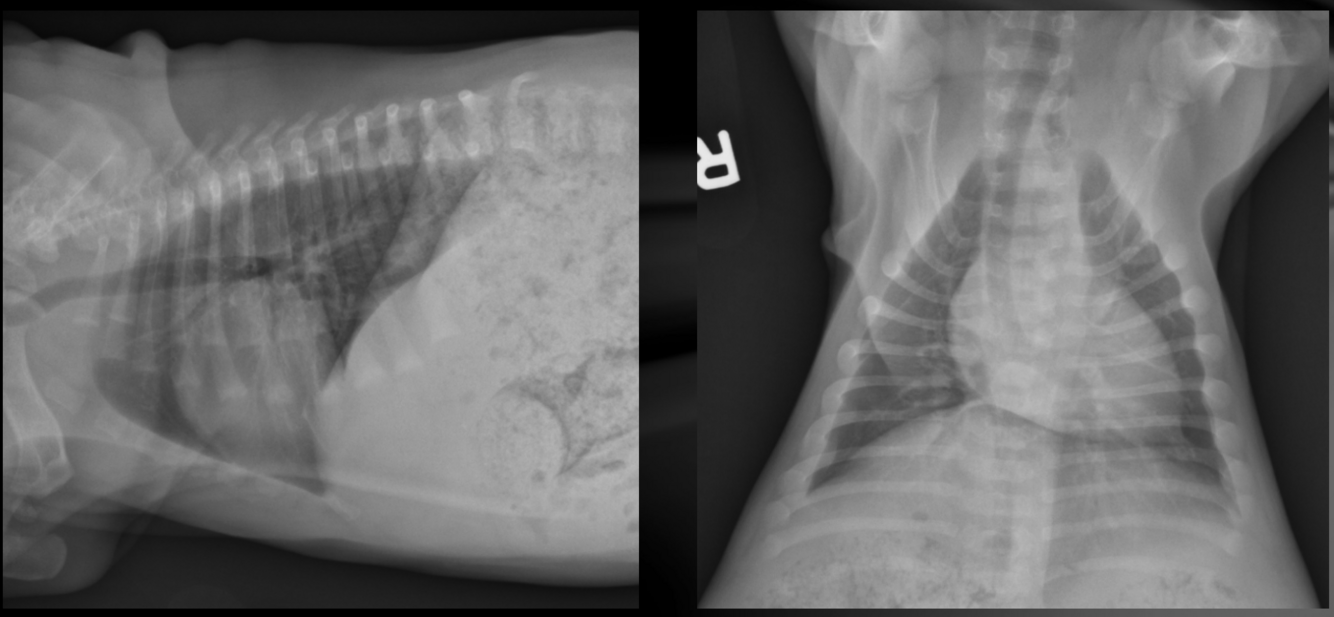

What is important regarding the ribs in these radiographs?

middle-aged dog; costal cartilages have mineralized but not excessively

old dog; costal cartilages show irregular, exuberant mineralization